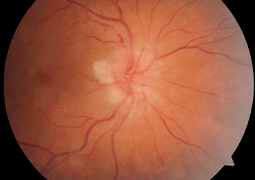

- Choroidální neovaskulární membrána u dětí, dlouhodobé výsledky terapie anti-VEGF preparátem

- Postradiačná makulopatia u pacientov s malígnym melanómom corpus ciliare a chorioidey po stereotaktickej rádiochirurgii